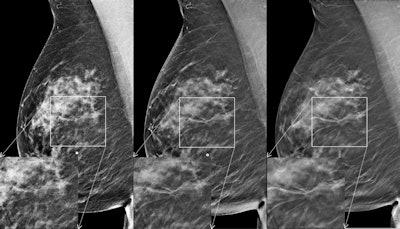

One solution is creating 2D mammography images from the 3D DBT data -- so-called "synthesized" 2D images -- via commercially available software. To evaluate the technique, a team led by Dr. Per Skaane, PhD, from the University of Oslo compared the diagnostic performance and radiation dose of conventional FFDM plus DBT with that of synthesized 2D images plus DBT for breast cancer screening.

Synthesized 2D exams produced during the first period were generated by an early version of C-View, while those in the second period were generated by an upgraded version, the authors wrote.

Having 2D mammography images in addition to the tomosynthesis images is important for many reasons, including the ability to compare priors to current exams, compare the right versus left breast, and provide current 2D exams to other institutions, according to Skaane and colleagues. And the evolution of synthesized 2D image software has made the use of these images with DBT even more viable for clinical practice.